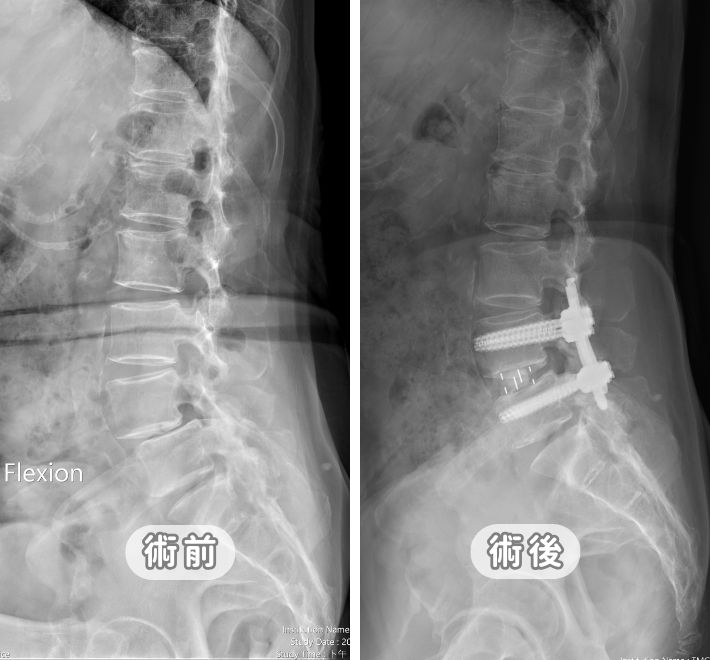

2. 核心手術方案:電腦導航微創腰椎融合術

針對不穩定的脊椎滑脫,這是目前的主流術式:

減壓:移除壓迫神經的增生韌帶或骨刺。

復位與融合:將滑脫的椎體推回原位,並在椎間盤空間置入支架,最後以導航精準鎖入螺釘固定。

優勢:患者通常術後隔天即可在護腰保護下下床活動,大幅縮短住院天數。